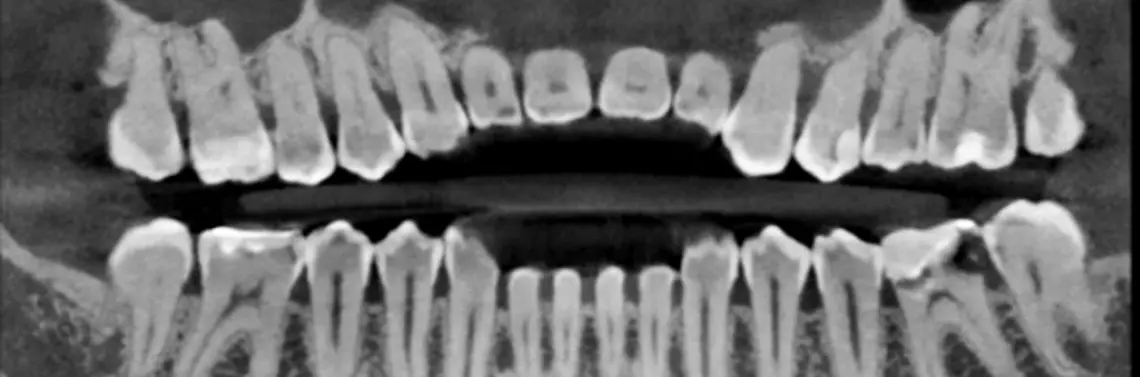

Jednym z głównych powodów, dla których tomografia komputerowa CBCT jest uznawana za bardzo dobrą, jest jej zdolność do dostarczania niezwykle precyzyjnych i trójwymiarowych obrazów struktur anatomicznych. Dzięki zastosowaniu stożkowej wiązki promieni rentgenowskich CBCT pozwala uzyskać obrazy o bardzo wysokiej rozdzielczości przestrzennej. Powszechnie stosowane są już rozdzielczości w rozmiarze woksela 75 (zdj. 1) czy 150 µ (zdj. 2). To umożliwia lekarzom bardzo precyzyjną analizę takich struktur, jak: kanały nerwowe, zęby, kości szczękowe czy stawy skroniowo-żuchwowe, co jest kluczowe w diagnostyce i planowaniu leczenia.